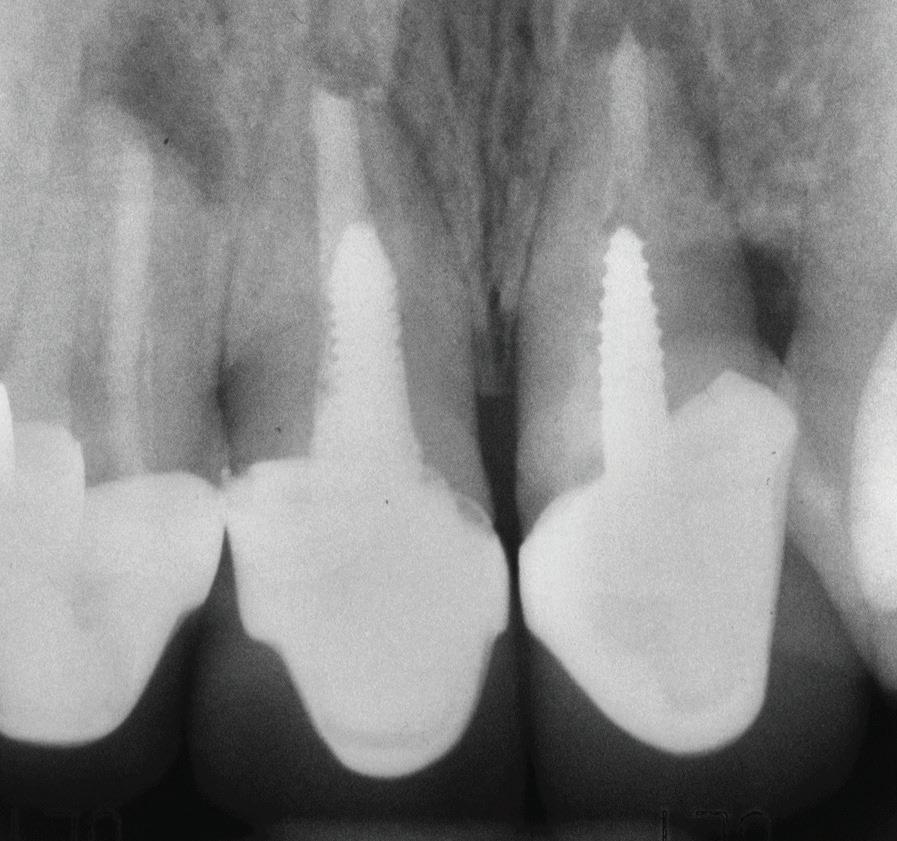

Un pacient caucazian în vârstă de 77 ani s-a prezentat la clinica autorului după cinci ani în care nu a fost la niciun control stomatologic. Examinarea clinică a arătat o pierdere semnificativă de os, parodontită cronică și multiple edentații care au destabilizat ocluzia. Pacientul a raportat sensibilitate la rece la nivelul primului molar drept inferior nr. 46, în special la ingerarea de lichide reci. Radiografia periapicală a confirmat constatările examenului clinic; în

plus, s-a detectat și prezența unei carii radiculare la nivelul rădăcinii distale a aceluiași molar, cu răspuns pozitiv la testul de sensibilitate (fig. 1-2).

Planul de tratament a început cu accent pe restabilirea sănătății parodontale. Într-o ședință ulterioară, odată cu îmbunătățirea stării parodonțiului, s-a efectuat restaurarea molarului nr. 46. Sub anestezie la Spina Spix pe partea dreaptă și

2. Radiografia inițială.